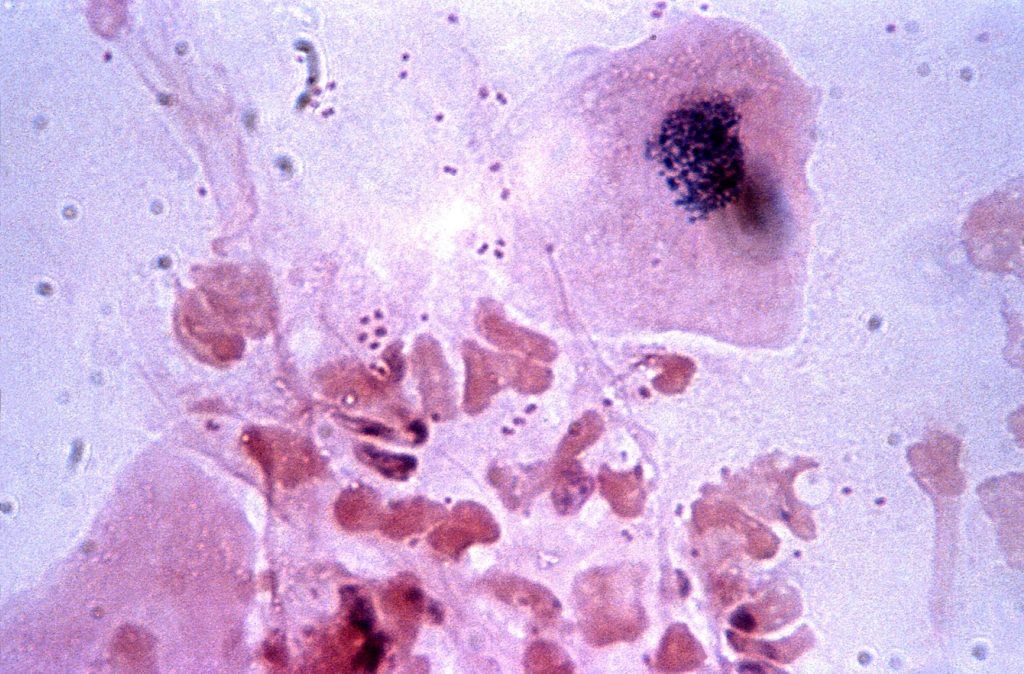

I leucociti, cioè i globuli bianchi, sono delle cellule contenute nel sangue. La funzione principale...